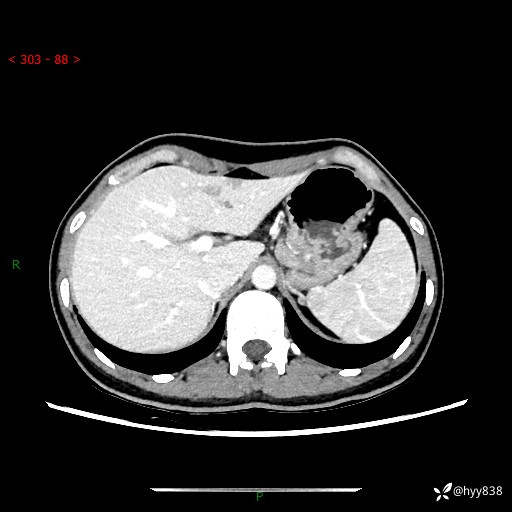

性别:女

年龄:23岁

简要病史:外院发现肝结节,来我院进一步增强确诊

上腹部CT平扫+增强